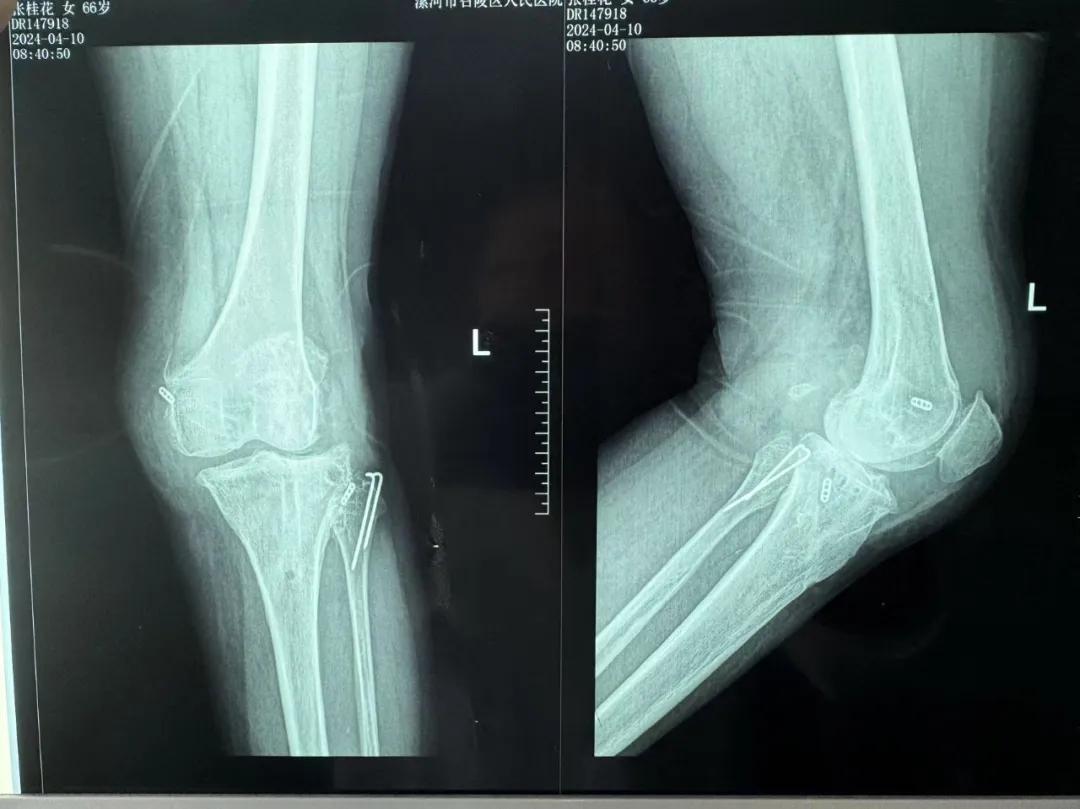

患者來(lái)院后,漯河市骨科醫(yī)院(漯河醫(yī)專二附院、漯河市立醫(yī)院)主治醫(yī)師康樂(lè)便成了她的管床醫(yī)生。在經(jīng)過(guò)詳細(xì)的術(shù)前診斷與檢查后,關(guān)節(jié)外科主任李付彬組織科室團(tuán)隊(duì)針對(duì)患者的診斷情況進(jìn)行術(shù)前討論——患者為重度膝關(guān)節(jié)骨關(guān)節(jié)炎,需進(jìn)行人工關(guān)節(jié)置換。但術(shù)前的評(píng)估結(jié)果顯示:患者膝關(guān)節(jié)側(cè)方不穩(wěn)定,單純行初次表面膝關(guān)節(jié)置換,術(shù)后仍會(huì)存在側(cè)方不穩(wěn)的情況,會(huì)影響術(shù)后效果以及假體使用年限,不僅無(wú)法完全恢復(fù)膝關(guān)節(jié)功能,還會(huì)加重患者的經(jīng)濟(jì)負(fù)擔(dān)。

為了盡可能給患者帶來(lái)更好的治療效果,減輕其經(jīng)濟(jì)負(fù)擔(dān),經(jīng)綜合評(píng)估后,李付彬主任帶領(lǐng)團(tuán)隊(duì)制定了最終的手術(shù)方案——決定使用髁限制性膝關(guān)節(jié)假體(LCCK)置換膝關(guān)節(jié)。作為解決患者病痛的最優(yōu)方案,這項(xiàng)手術(shù)具體實(shí)施的難度并不小,需要在術(shù)中根據(jù)截骨情況進(jìn)行多次評(píng)估和實(shí)時(shí)調(diào)整,這就要求主刀醫(yī)生不僅要具備過(guò)硬的專業(yè)技術(shù)與能力,還要能夠結(jié)合自身的經(jīng)驗(yàn)準(zhǔn)確判斷、精準(zhǔn)操作。

手術(shù)過(guò)程中,關(guān)節(jié)外科團(tuán)隊(duì)為患者進(jìn)行了標(biāo)準(zhǔn)截骨,經(jīng)過(guò)評(píng)估,患者膝關(guān)節(jié)仍存在膝關(guān)節(jié)側(cè)方不穩(wěn)定,便按照原定手術(shù)計(jì)劃使用LCCK假體進(jìn)行了膝關(guān)節(jié)置換。經(jīng)過(guò)再次評(píng)估,患者膝關(guān)節(jié)穩(wěn)定性恢復(fù),下肢力線正常,這臺(tái)高難度的LCCK膝關(guān)節(jié)置換手術(shù)在一小時(shí)內(nèi)便順利完成!術(shù)后第二天,患者就能夠自主下床負(fù)重活動(dòng),功能恢復(fù)良好。